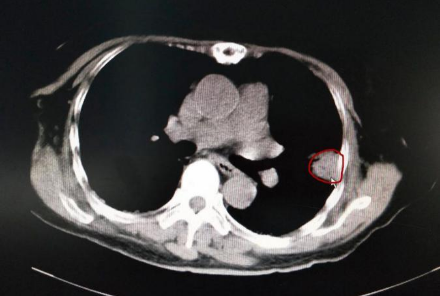

患者李阿姨今年4月复查提示左肺结节增大,7月复查被告知胸部CT示“双肺间质纤维化伴感染,与前片对比未见明显变化;左肺上叶肿块,病变增大;经皮肺穿刺活检病理示‘肺腺癌’,EGFR示‘19外显子突变’,PD-L1(-),诊断‘左上肺腺癌T2aN0M0ⅠB期’”。

手术前李阿姨肺部CT片